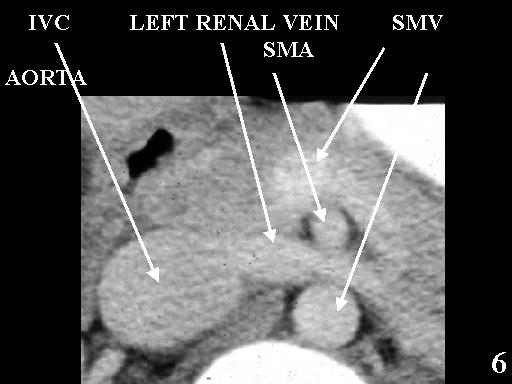

MS 190 CT 17